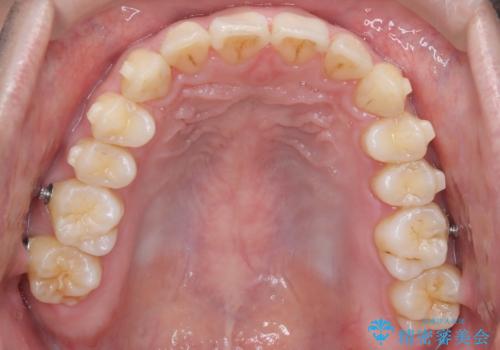

- 前歯が出ていることを主訴に来院されました。

歯列の幅が狭かったため、横に広げながらスペースを作り、叢生の改善を行いました。

左側の犬歯関係も治療前より良い状態で治療を完了することができました。

今回は臼歯部の遠心移動を行うために2級ゴムを使用しています。